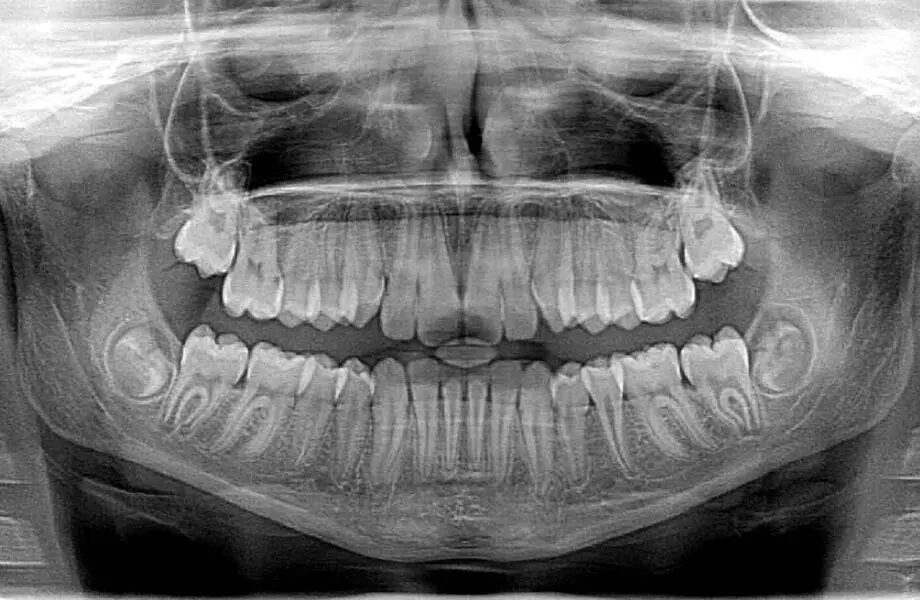

راهنمای جدید استفاده محتاطانهتر از رادیوگرافی در دندانپزشکی

هر کسی که به طور منظم از خدمات دندانپزشکی استفاده کرده باشد، با پیشبند سربی سنگینی که قبل از گرفتن عکس رادیولوژی از دندانهایش روی بدنش میپوشد، آشناست، اما این منظره ممکن است تغییر کند.